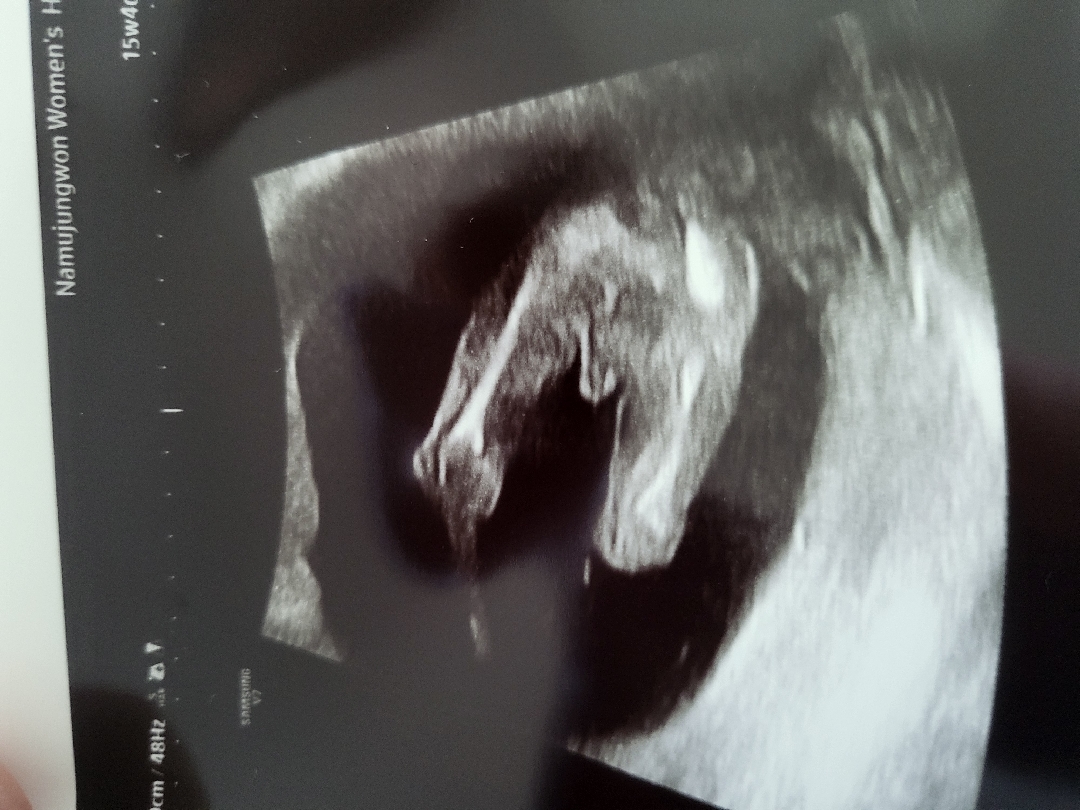

성별확인 하는날 딱 15주4일차 가서봤더니 딱보여줘서 아들인걸 확정했네요